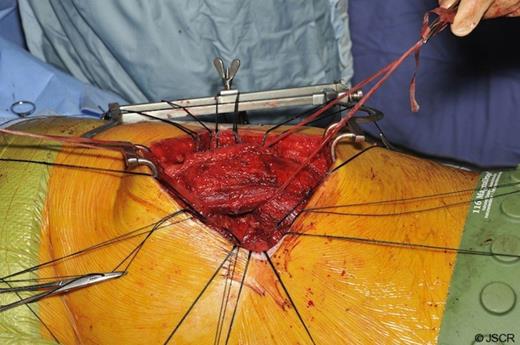

A limited left muscle sparing postero-lateral thoracotomy was used to gain access to the chest. Both the serratus anterior and latissimus dorsi muscles were mobilised and preserved (figure 3). The fractured portions of the seventh and eighth ribs were dissected and subsequently resected. The sixth rib, deemed to be healing appropriately and in-keeping with normal anatomy, was spared.

Next, the site of the lung herniation was identified (figure 4) and interrupted anchoring sutures were lain down (figure 5).